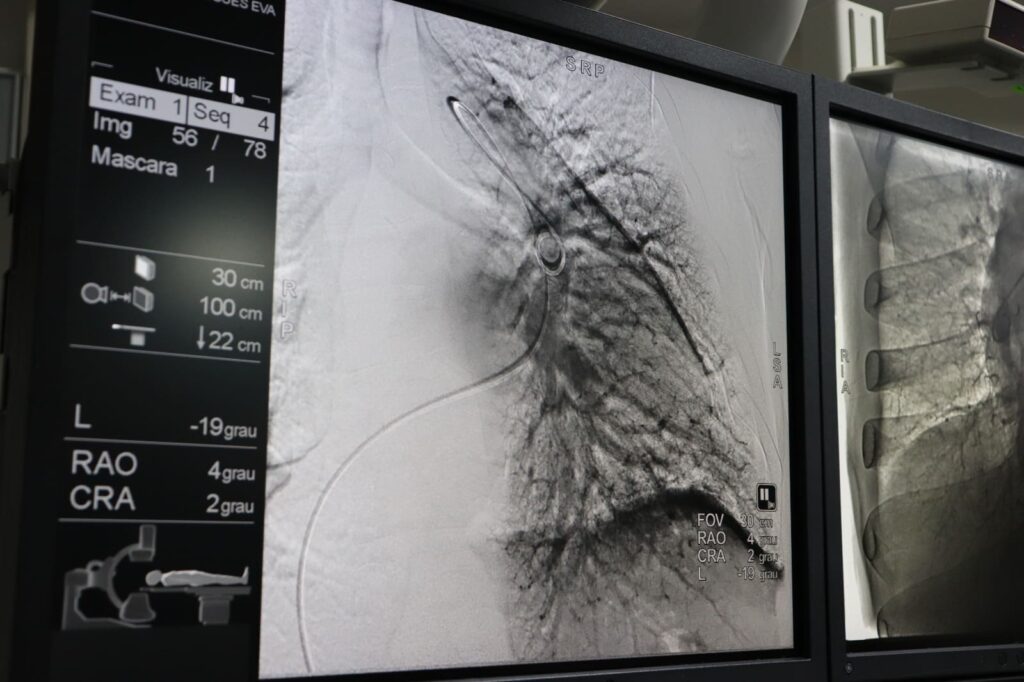

HGG é o único hospital público a realizar angioplastia pulmonar por balão em Goiás

Procedimento recomendado para pacientes com hipertensão pulmonar já é feito na unidade do Governo de Goiás, após capacitação realizada por cardiologista intervencionista da Universidade Federal da Bahia